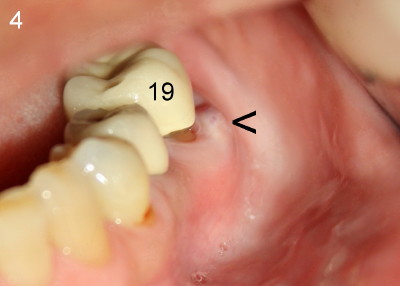

When attention was turned to the left side of this patient, chronic infection was noticed near the buccal furca of the tooth #19 (Fig.4: arrowhead). As a matter of fact, this type of infection has persisted for five years (Fig.3: arrowheads). Extraction of the tooth #19 has not been done because of mild and periodic discomfort. In contrast, signs and symptoms associated with the tooth #30 were more severe and acute, leading to extraction. Ideally, #19 should be extracted prior to or during #30 implant placement to prevent post-implant infection.